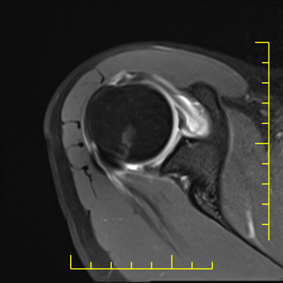

22. veljače 2026.Artrografija zglobova je specijalizirana dijagnostička metoda kojom se uz primjenu kontrastnog sredstva detaljno prikazuju strukture unutar zgloba – hrskavica, labrum, ligamenti, kapsula i tetive.

Artrografija je dijagnostički postupak u kojem se pod kontrolom RTG-a ili ultrazvuka u zglob aplicira kontrastno sredstvo, a zatim se izvodi magnetska rezonancija (MR) ili kompjutorizirana tomografija (CT).

- jasniji prikaz puknuća labruma

- detekciju sitnih lezija hrskavice

- procjenu nestabilnosti zgloba

- otkrivanje parcijalnih ruptura tetiva i ligamenata

Artrografija ramena

MR artrografija ramena smatra se zlatnim standardom za dijagnostiku ozljeda labruma i nestabilnosti ramena.

Što se najbolje prikazuje

- glenoidni labrum

- zglobna kapsula

- parcijalne rupture rotatorne manžete

- unutarnja oštećenja hrskavice

Kod mladih i aktivnih pacijenata artrografija često otkrije promjene koje nisu vidljive na standardnoj MR pretrazi.